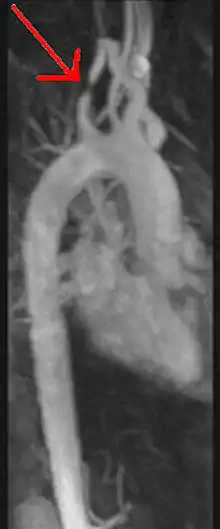

آنژیوگرافی تشدید مغناطیسی

آنژیوگرافی تشدید مغناطیسی (به انگلیسی: Magnetic Resonance Angiography) و (به اختصار MRA)، روشی برای تصویربرداری (رگ نگاری) در پزشکی است. به تصاویر تولید شده بهوسیله این روش مغناطیسی گویند.